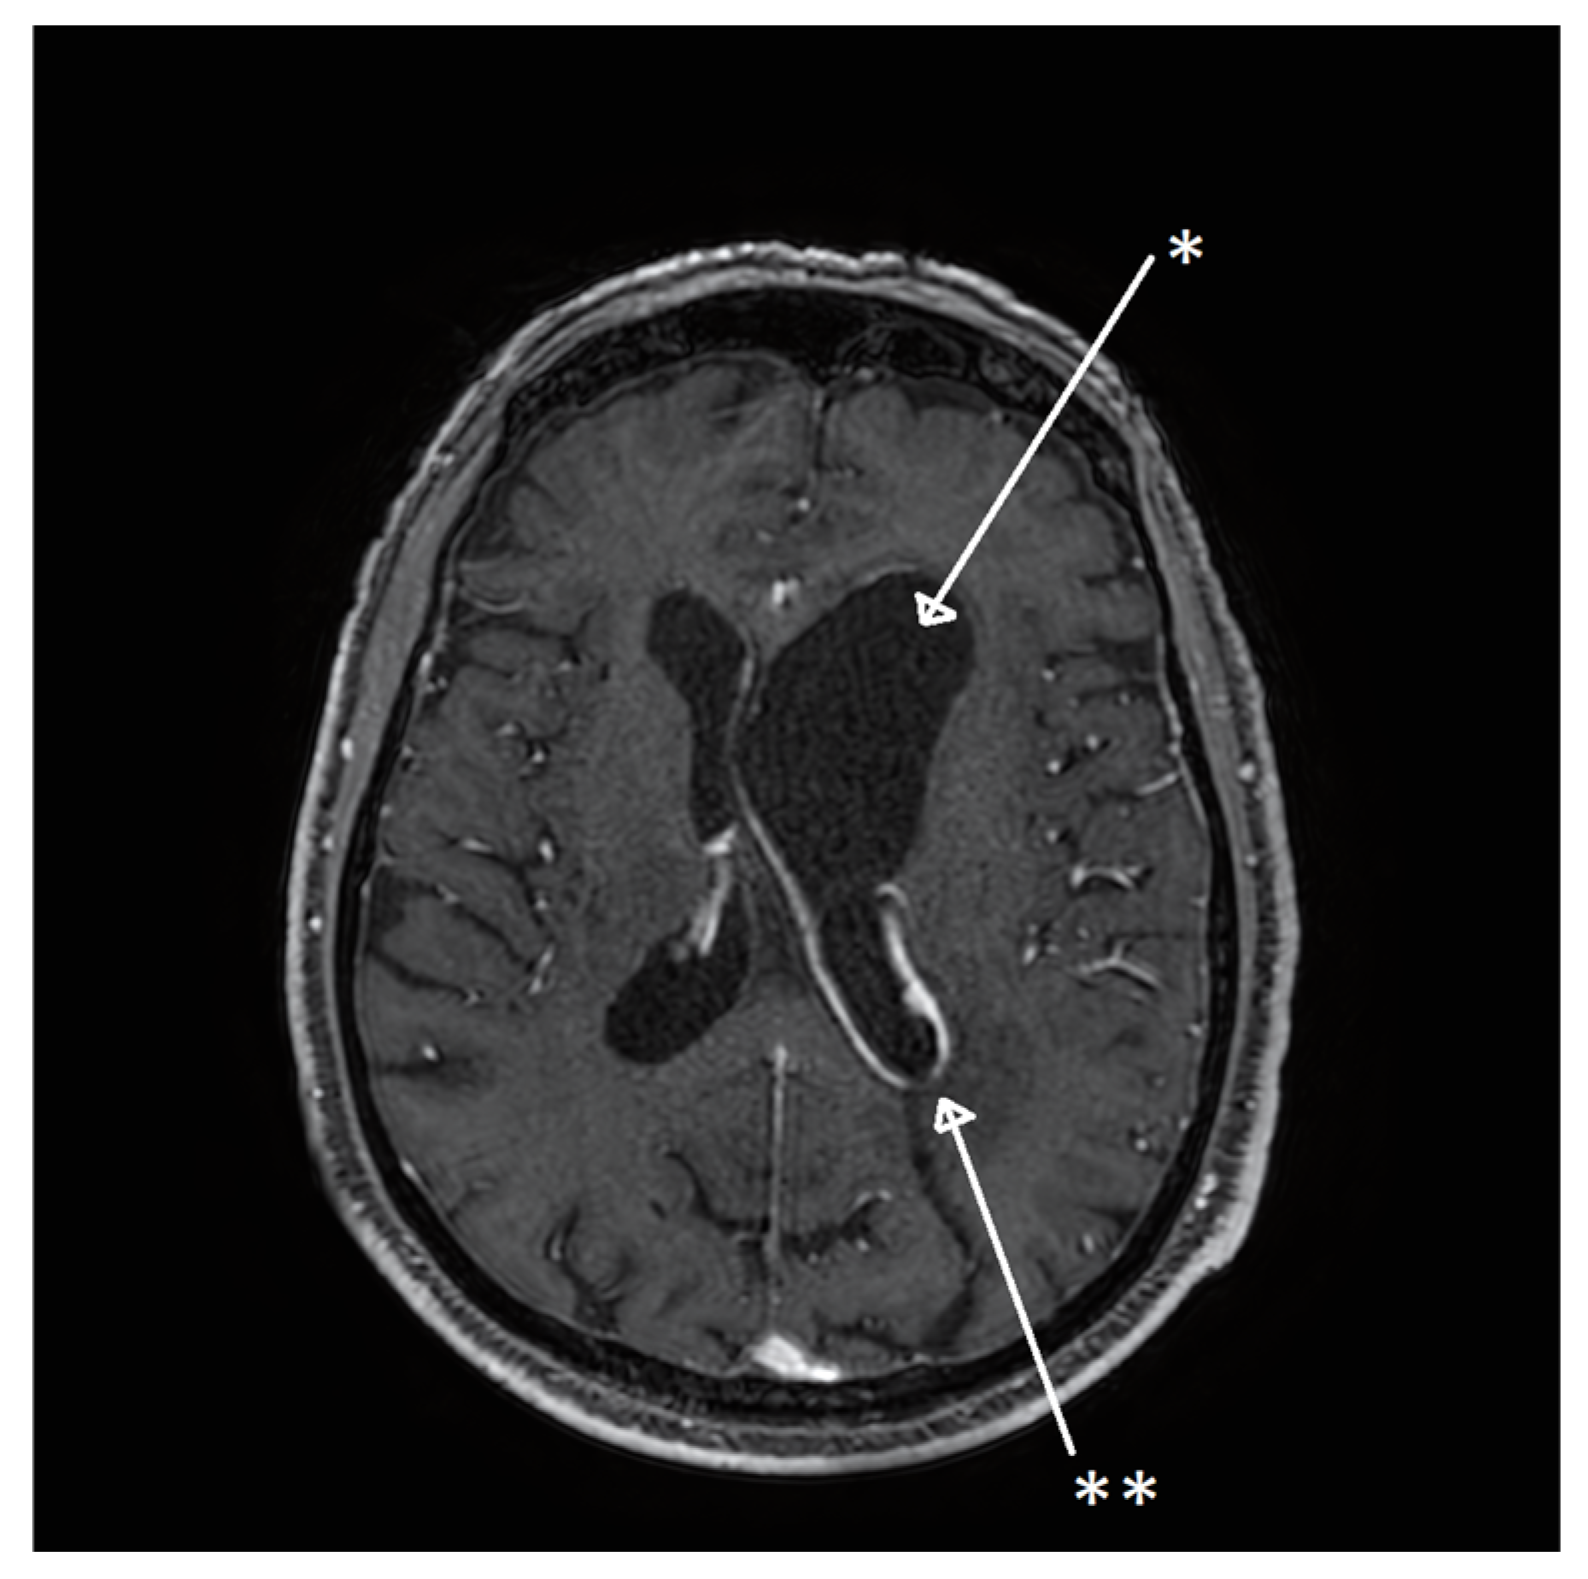

| 8 | Our case | 77/M | Fever, confusion | Right frontal lobe hyperintensity and left lateral ventricle exclusion. | Encephalitis and ventriculitis | CSF | Pleocytosis, hypoglycorrhachia, and hyperproteinorrachia | INH + RIF + EMB + LEV; LIN (2 weeks) | No | Yes | 14 | SR |